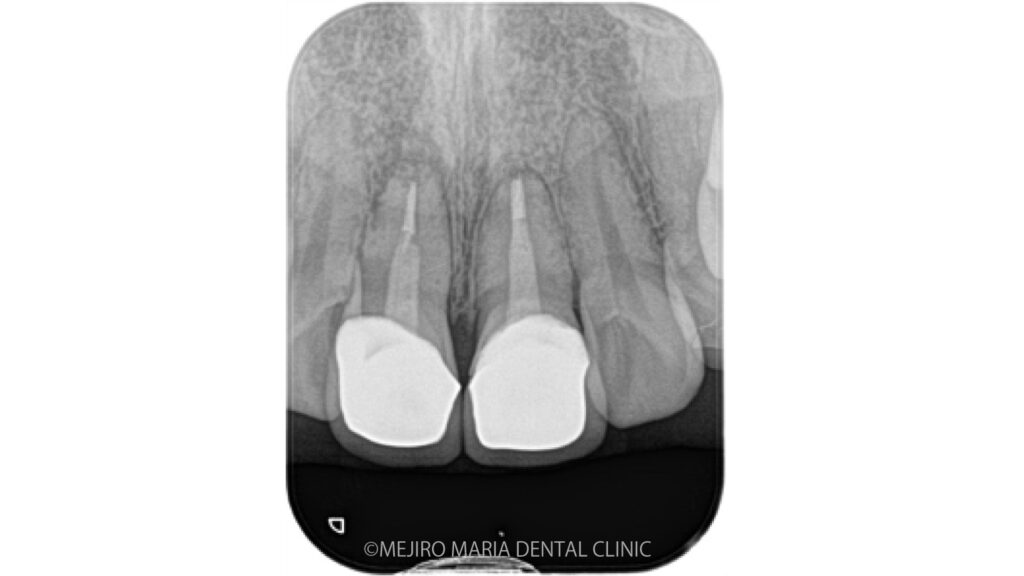

当院を受診する前にも根管治療を行なっている歯科医院を受診するも、抜歯しインプラントを勧められたとのことでした。当院の診査では抜歯をするほどの所見は確認できず、通常通りの精密根管治療を行うことをご提案させていただきました。

当院にて根管治療を開始するも根管治療の反応は乏しく、術前に確認できていた症状の改善は認められませんでした。その為、この患者様には歯根端切除術を追加で行い、マネージメントをさせていただくこととなりました。

歯根端切除術時に根尖を3mmほど切断したところ、根尖を取り囲むほどの歯石が確認され、この歯石の感染が根尖性歯周炎の治癒を妨げていた可能性がありました(写真)。

今回の症例は長期間病状を放置してしまった結果、根管の外に歯石が形成され、根管治療のみで治癒させることができず、次いで歯根端切除術を行うことで治癒に導いた症例です。

根尖孔外(根の外)に感染源がある場合根管内部の洗浄をいくら行ったとしても感染を除去することは出来ません。その為、根の治療の訓練を受けた専門医が根管治療を施しても改善が認められない場合は速やかに歯根端切除術へ移行することが望ましいと考えられます。